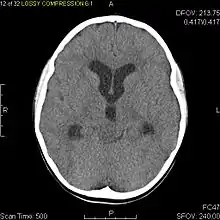

| Diagnostic method | MRI, CT scan |

Usually – depending on the interview of the patient and after a clinical exam which includes a neurological exam and an ophthalmological exam – a CT scan and/or an MRI scan will be performed to confirm the presence of a tumor. They are usually easily distinguishable from normal brain structures using these imaging techniques. A special dye may be injected into a vein before these scans to provide contrast and make tumors easier to identify. Pilocytic astrocytomas are typically clearly visible on such scans, but it is often difficult to say based on imaging alone what type of tumor is present.